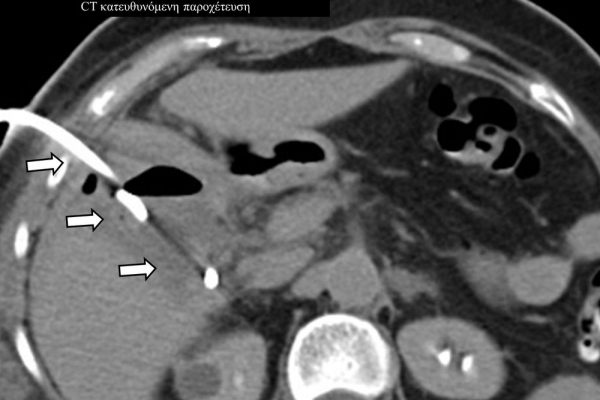

Η παρέμβαση διενεργείται υπό την καθοδήγηση αξονικού τομογράφου ή υπερήχων ή και με συνδυασμό τους. Ο επεμβατικός ακτινολόγος αρχικά αναισθητοποιεί την ανατομική περιοχή ενδιαφέροντος με τη χρήση τοπικής αναισθησίας και παρακεντεί την συλλογή διαδερμικά με λεπτή βελόνη. Στη συνέχεια μέσω ομοαξονικών συστημάτων συρμάτων-καθετήρων-διαστολέωντοποθετείται διαδερμικός καθετήρας τύπου pig-tail εντός της συλλογής, ο οποίος συνδέεται με εξωτερική παροχέτευση.